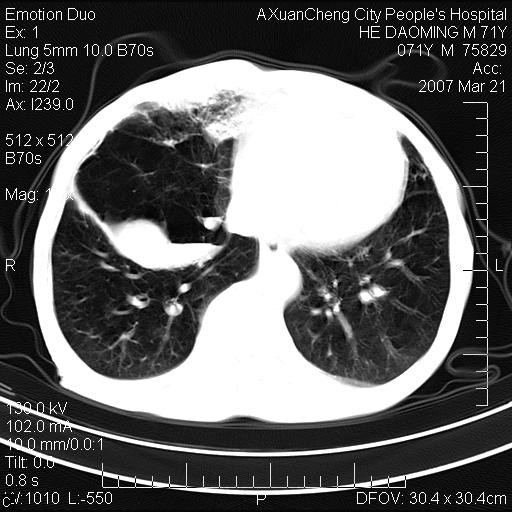

标题: CT7269:[原创] 咳嗽,咳痰,大家讨论右肺病变的部位

右侧相当于叶间软组织样密度ct值约50hu,请大家讨论是什么性者病变

考虑:慢性支气管炎合并全小型肺气肿、肺大泡、间质纤维化、感染,右斜裂积液。

考虑慢支,肺气肿,肺大泡,间质纤维化;右侧斜裂液气胸考虑(可能因为肺大泡破裂破入斜裂所致).

考虑病变以右上中肺多发肺大泡为主并感染。请结合临床考虑慢支肺气肿,肺心病。

考虑:慢性支气管炎合并右侧全小型肺气肿、肺大泡并感染、双肺间质纤维化,右斜裂积液。

如果患者变化一下体位扫描可分辨液平与斜裂的关系。